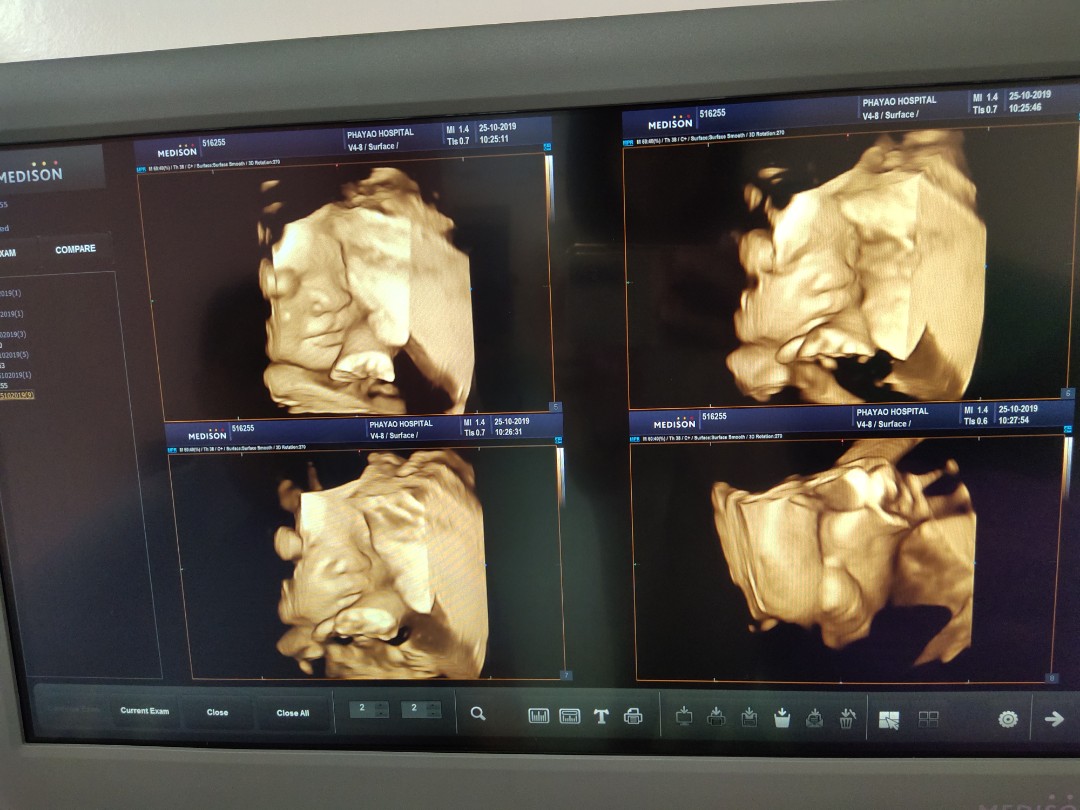

ใบซาวด์

ขอดูใบซาวด์แม่เพศ ชาย หญิง หน่อยค่ะ

ผ.ชค่ะภาพสุดท้าย

หมอบอกผู้ชายค่ะ

บ้านนี้ชายจ้าาา

จู๋ใหญ่มากค่ะ

ผู้ชายคะ

แฝดชายคู่จ้า